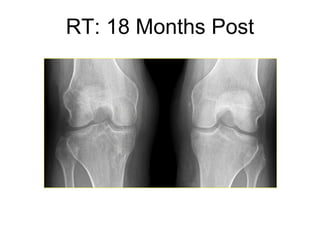

Excellent joint space, intact meniscus allograft and ACL, but right knee clicking and catching RT: 18 Months Post

Intact meniscus allograft and ACL with diffuse thinning of patellofemoral cartilage RT: 18 Months Post

Surgery for catching due to chondral flap at patellofemoral joint Intact meniscus allograft and ACL RT: 18 Months Post